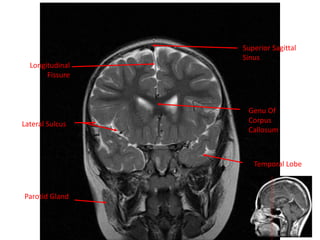

Longitudinal

Fissure

Superior Sagittal

Sinus

Lateral Sulcus

Parotid Gland

Genu Of

Corpus

Callosum

Temporal Lobe